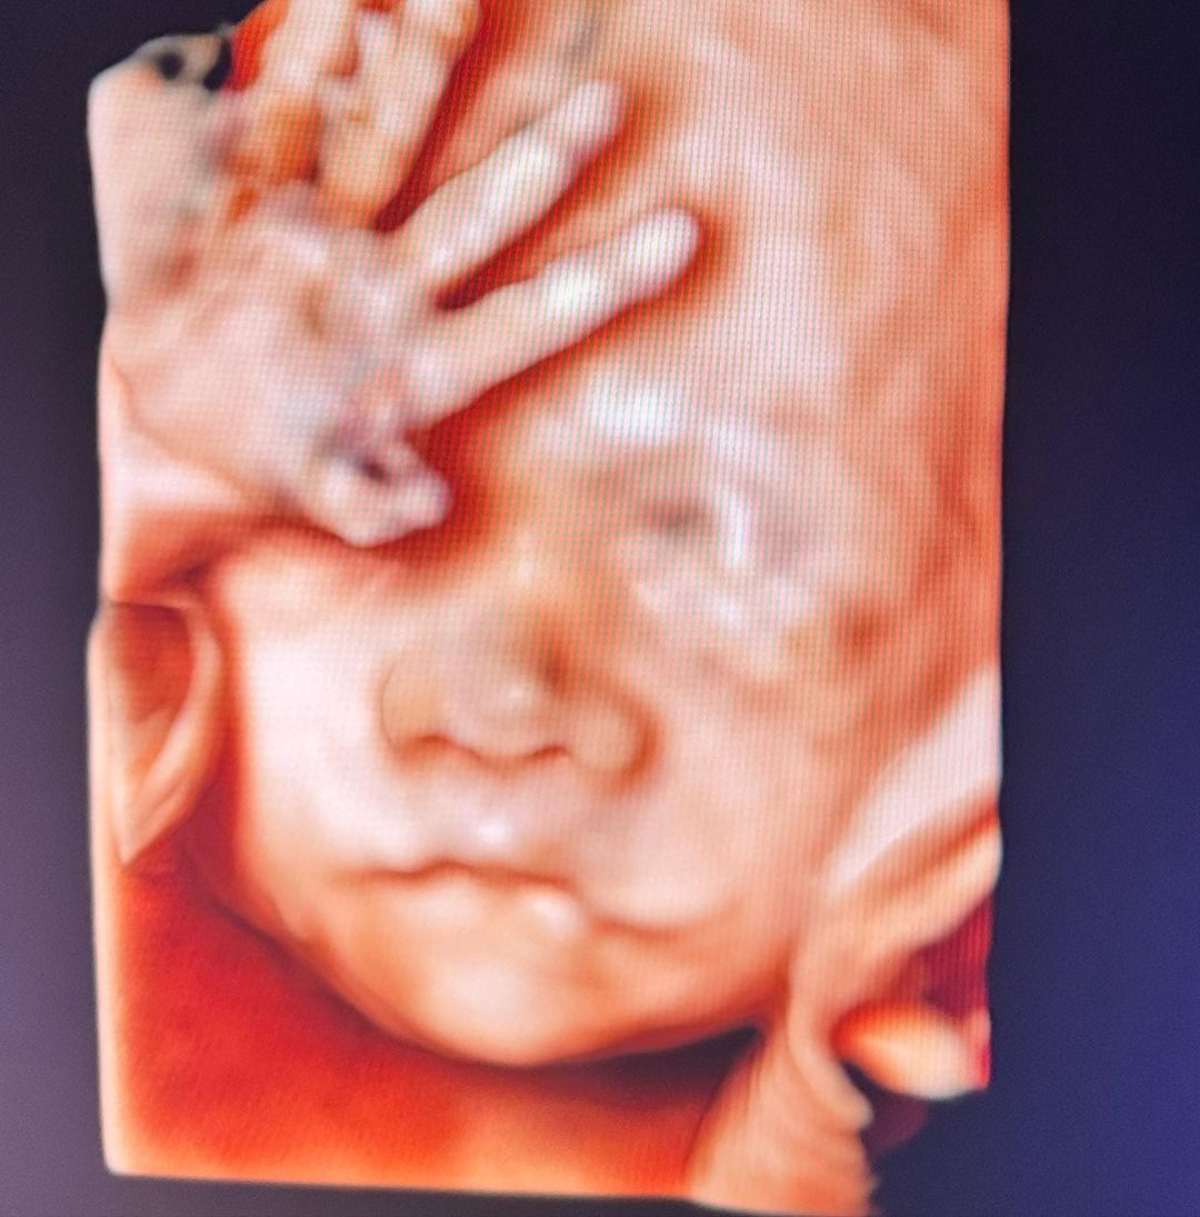

En esa línea, recientemente Vale Roth mostró una nueva ecografía, en la que ya se puede apreciar el rostro de su bebé y una de sus manitas.

"Así que acá me pueden ver en mi semana 25, estoy pesando 740 gramos y mido 33 cm. Estoy muy grande y seguiré creciendo", añadió.